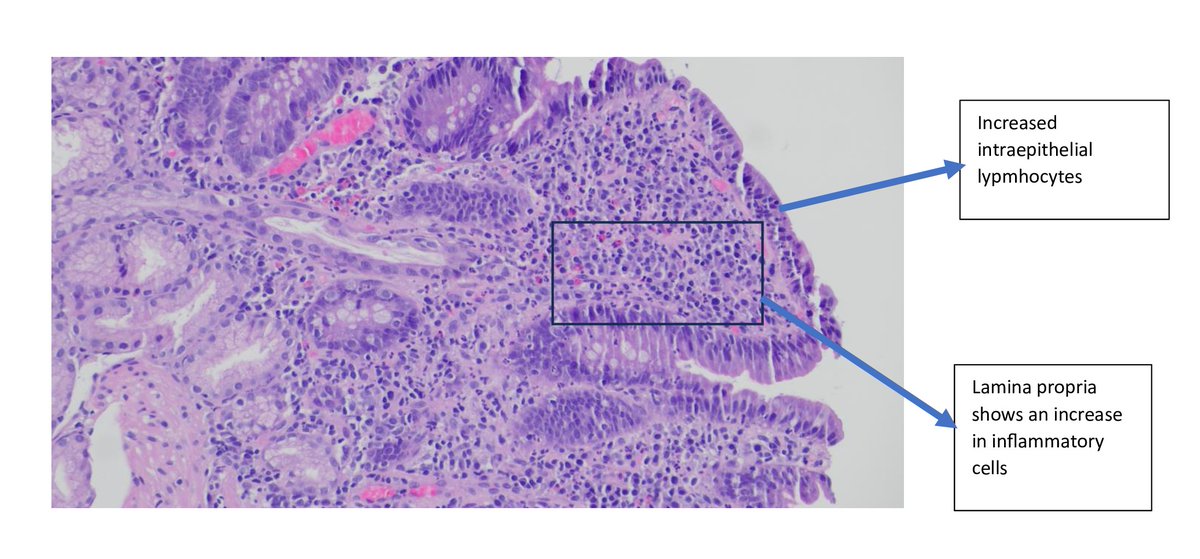

🚨 A 54-year-old woman on #Olmesartan for hypertension developed unexplained GI symptoms. Celiac serology was negative. It turned out to be Olmesartan-induced enteropathy.🩺 #PathTwitter #MedTwitter